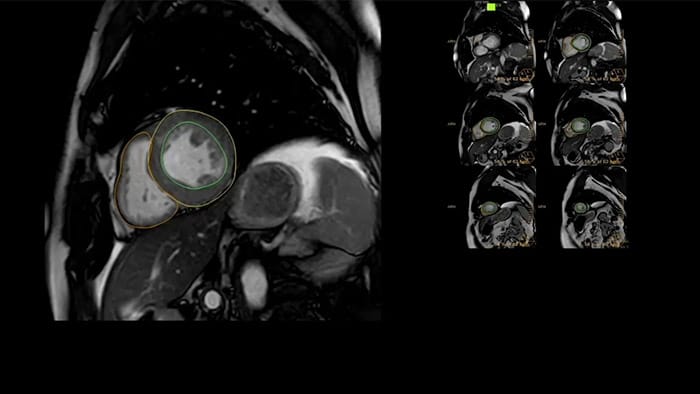

IntelliSpace Portal offers a Comprehensive Cardiac MRI Suite, providing dedicated workflows for functional analysis, viability, LGE, cardiac mapping assessment and RV/LV functional analysis in less than 5 min. per case1.

IntelliSpace Portal MR Caas5,6 Strain7 assists in patient diagnosis and monitoring by providing global strain parameters such as global longitudinal strain (GLS), global circumferential strain (GCS), and global radial strain (GRS), using short and long axis MR images, as well as describing the myocardium deformation- such as shortening, thickening, and lengthening during the cardiac cycle.